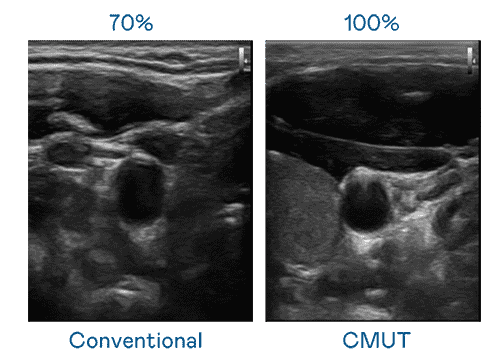

CMUT 技术是一种用电容式微机电元件来产生超音波讯号的技术。。。。与传统 PZT 压电式技术相比,,,,CMUT 频宽增加 30%,,更宽频的超音波讯号让影像解析度大幅提升,,,,是实现高影像品质医疗超音波扫描、、、促进精准医疗发展的关键技术。。。。

大频宽带来超清晰影像

超音波影像的解析度高低,,,,首先取决于探头能发出的讯号频宽。。。万利 CMUT 可提供高清晰的超音波讯号,,提供高频宽、、高灵敏度、、影像纹理细节更高的超音波影像,,协助医护人员缩短影像判读时间及利用精准的医疗影像进行诊断。。。。